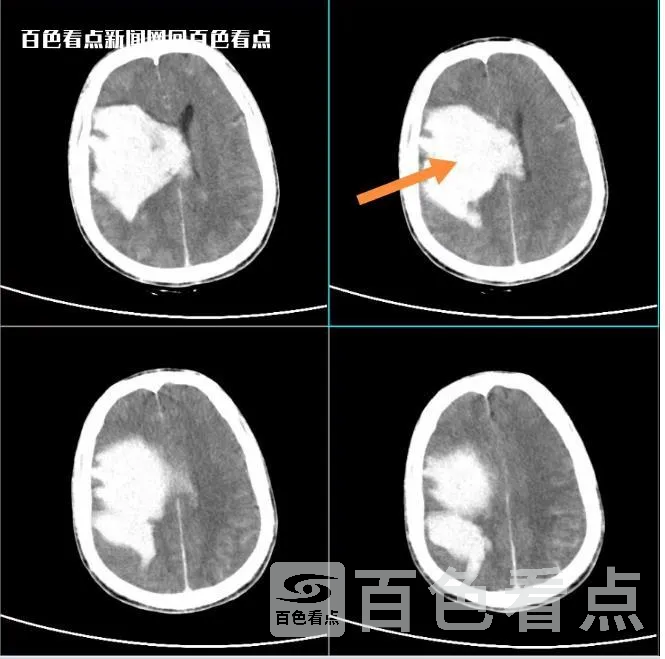

患者李某抵达右医附院后,右医附院神经外科ICU医务人员立即为李某安排了急诊检查,结果考虑脑内巨大动静脉畸形破裂并大量脑出血,病情评估为危重级,患者双侧瞳孔不等大,生命征不平稳,脑疝形成,随时可能会出现心跳呼吸骤停等风险。

病人脑部出血量达到惊人的200ml

罗起胜博士团队立即组织医护团队详细商讨治疗方案。罗起胜博士指出,李某由于巨大脑内脑动静脉畸形破裂,导致大量脑出血。一般而言,脑部出血量达到30ml就要进行手术,但现在患者的脑部出血量已经达到了惊人的200ml,并且已经破入脑室系统。若不及时清除血肿解除颅内高压,患者随时呼吸心跳骤停而死亡。若延误救治时间,则影响患者预后,患者术后可能会产生偏瘫、失语、肢体功能障碍、智能障碍甚至植物生存,治疗必须争分夺秒,井然有序,而且刻不容缓。当务之急是要通过精准血管探查找出脑部出血点,先行颅内动静脉畸形栓塞术,从源头杜绝出血点,然后再进行第二次手术,机器人辅助神经内镜下开颅清除血肿。